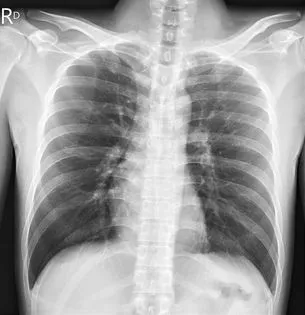

醫師蘇一峰今(12)日在臉書發文,有一名30歲男子在高中大學是體保生,今年一月感染新冠肺炎時只是輕症,但是一周後開始很喘,兩周後變成臥床,一動就喘,接下來連續三個月都不能動,到處檢查都沒有問題,只能坐著輪椅來就診。

「新冠康復後會喘但X光正常?」蘇一峰說,研究發現肺部血流不足,他開立壯陽藥犀利士治療,目前吃藥有效,病人漸漸不喘了!已經正常生活自理,也能站起來了!